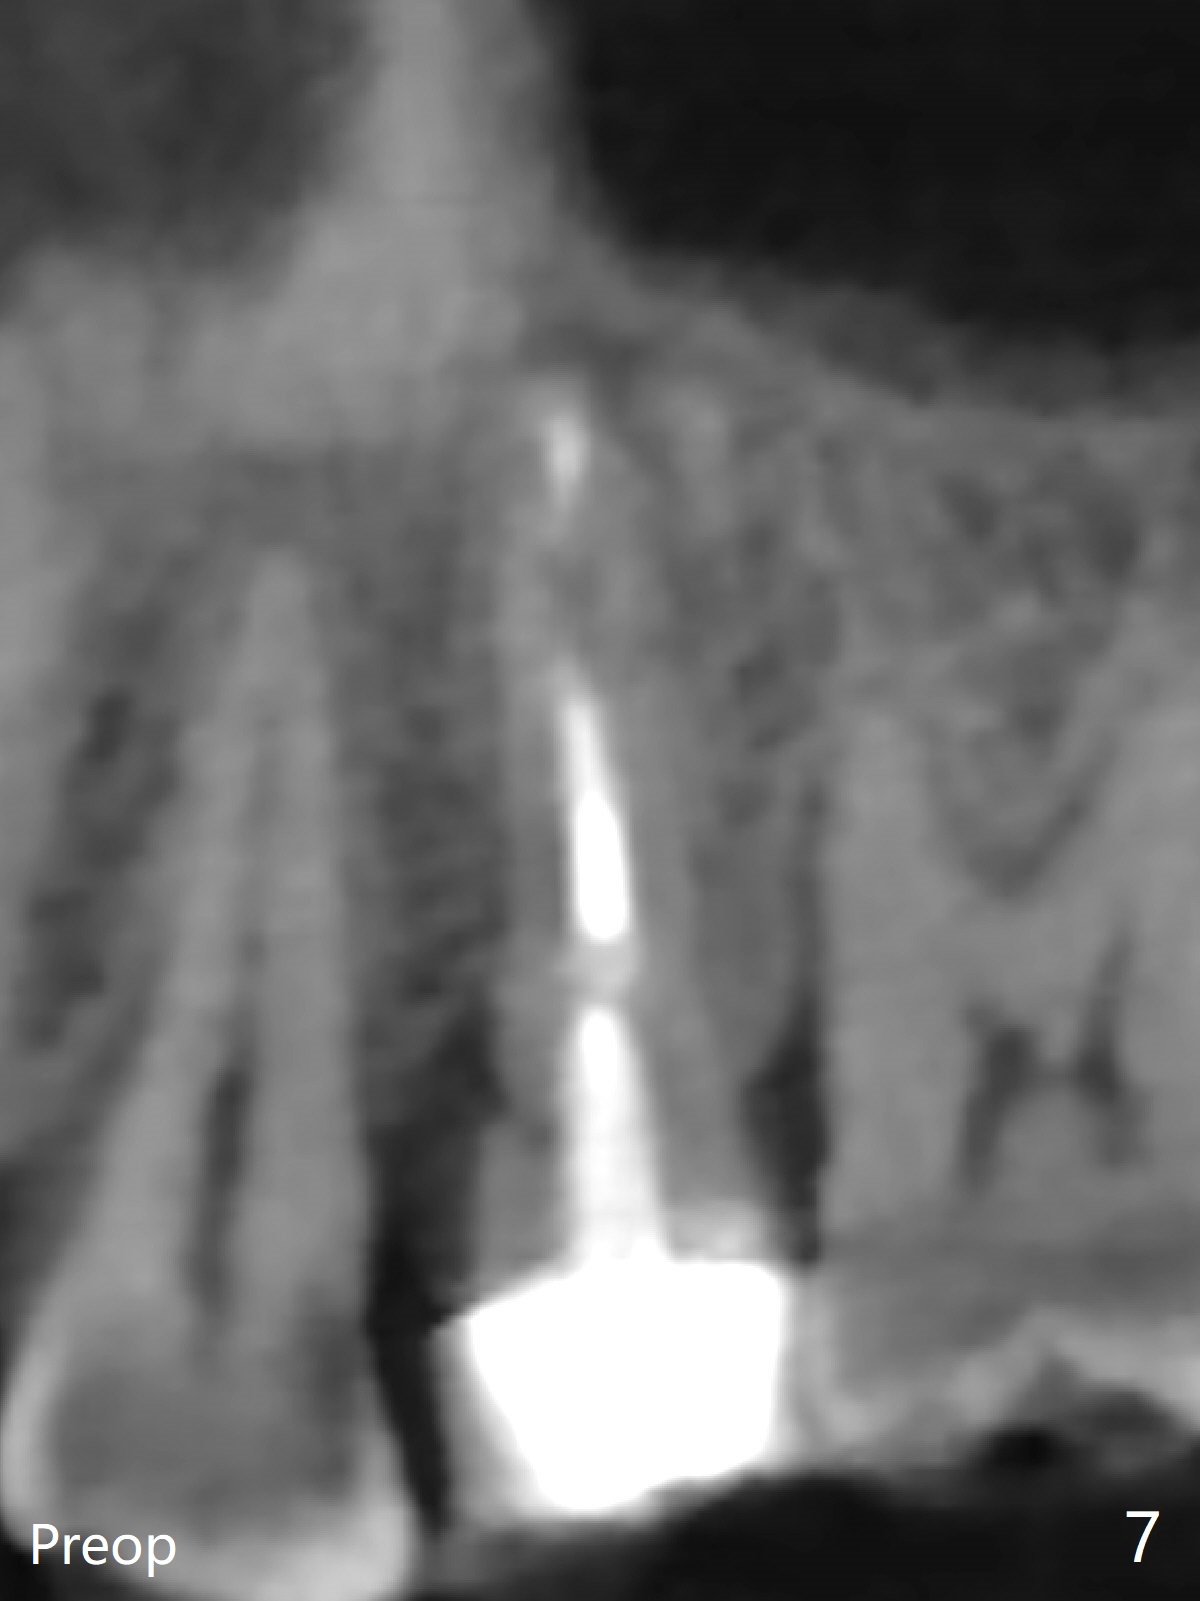

DIO lab refuses fabricating guide because of the large socket and recommends extraction and socket preservation at #13. Due to short apical bone (Fig.5,7), a long dummy implant (3.8x15 mm) is placed with periimplant space immediately post extraction (Fig.1 *). The final implant is larger (4.5x15 mm) with simultaneous sinus lift and periimplant bone graft (Fig.2,6,8 *). To repair the palatal crest defect (Fig.3 *) associated with tooth fracture (Fig.5 white dashed line), the implant is not placed too palatal with sufficient amount of the bone graft (Fig.4,6 *). The native bone (higher in bone density, Fig.9 white arrowheads, as compared to black one (for bone graft)) appears to have grown into the space between implant threads 5.5 months postop. The permanent crown/abutment is loose 1 year 9 months post cementation; after proximal reduction (Fig.10 arrowheads), the abutment is reseated completely. Pick up impression is taken and a healing abutment is placed. A few days later, the crown and abutment (separate) are seated passively; the abutment screw is retightened; the crown is re-cemented. The crown and abutment is removed for residual cement removal (Fig.11). Since there is mild buccal plate atrophy (Fig.11 B), the crown has a buccal lip (Fig.12 B) to prevent food impaction. The lip makes it difficult to remove residual cement intraorally. Therefore an access hole is necessary (Fig.13).